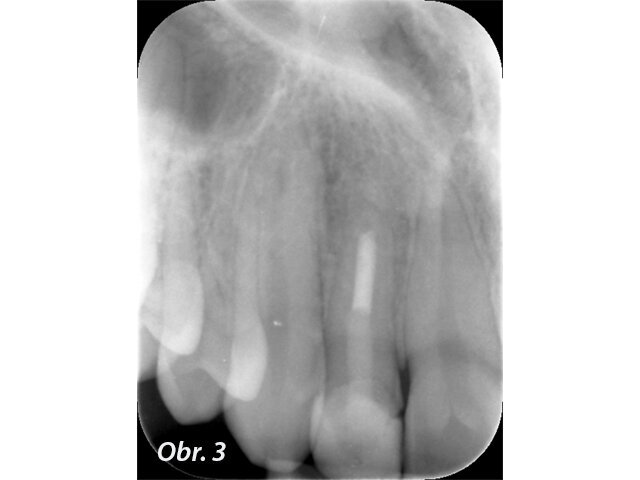

Prvním možným řešením je umístění MTA přímo do dekontaminovaného apexu zubu. U kratších rovných kořenů jde se správným instrumentáriem o poměrně snadný výkon. V případě 12letého chlapce referovaného po fraktuře zubu šlo ale o postranní řezák 12 s výrazným apikálním zahnutím, kam bylo s rigidní zahnutou koncovkou tzv. „MTA gun“ v roce 2011 nemožné aplikovat dostatečně hluboko. V dnešní době s flexibilními koncovkami MAP systému by zřejmě tento problém neexistoval. Přestože nebyl zub zcela zaplněn, předchozí dekontaminace a potentní dětská tkáň zajistily, že se veškerý zbývající prostor kořene vyplnil zřejmě dentinoidní tkání. Zub byl opatřen adhezivní dostavbou s FRC čepem a pryskyřičnou korunkou. (Obr. 1–3)

Popsané řešení má výbornou prognózu.